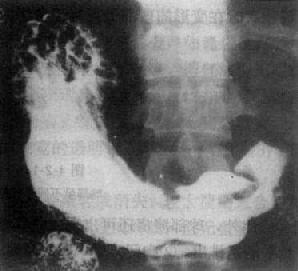

增殖型肠结核主要表现为肠和升结肠的狭窄、缩短和僵直。粘膜皱襞紊乱、消失,常见多数小息肉样充盈缺损,代表肠壁的肉芽组织增生。回盲瓣常受侵犯,表现为增生肥厚,使盲肠内侧壁凹陷变形,末段回肠扩大以及小肠排空延迟。如末段回肠受累,也可造成短段的狭窄与僵直以及皱襞的紊乱和息肉样改变,钡剂灌肠时上述改变恒久不变(图4-2-19)。

图4-2-9 肠结核(增殖型)

盲肠管壁增厚、管腔狭窄,欠规则,位置固定